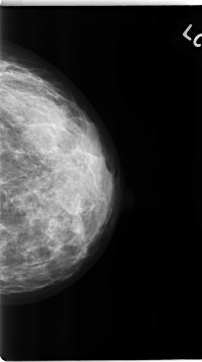

C_0139_1.LEFT_MLO

LEFT_MLO LINES 4696 PIXELS_PER_LINE 2592 BITS_PER_PIXEL 12 RESOLUTION 50 NON_OVERLAY